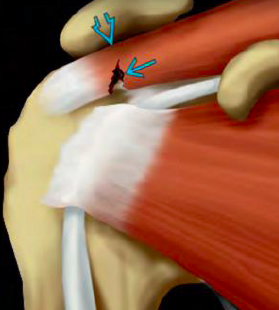

Causa más común de omalgia

Desgarro del manguito rotador

Causas etiológicas de desgarro del manguito rotador

• Traumatismo: agudo, crónico

Tendones que forman al manguito rotador

• Supraespinoso

• Infraespinoso

• Redondo menor

• Subescapular

• Accesorio: tendón largo del biceps